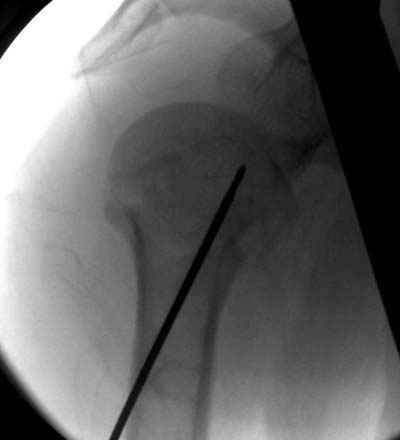

Сегодня взял больного повторно в операционную, не скажу, что повторная репозиция через неделю после первой попытки, была простая.

После удаления спиц попытался манипулировать отломками, но безуспешно, поэтому пришлось пользоваться периостальным элеватором, чтобы устранить смещение отломков и перепровести спицы. Проверил и перепроверил стабильность фиксации под ЭОПом, завтра Рг- будет готов, вот и поглядим....

Посылаю послеоперационные Рг граммы.

Всего Доброго,

Поздравляю, получилось просто замечательно. Если можно, расскажи чуть подробнее, как делали - как вправляли, как вводили спицы, поворачивали ли их?

Я и сам доволен результатом. В предпоследнем письме я кратко описал ход операции - закрыто репонировать не удалось( 2 недели с момента травмы и 1 неделя после неудачной репозиции) после удаления пучков спиц, пришлось сделать - 2см разрез на уровне перелома и с помощью периостального элеватора (золотое правило механики) *одеть* головку на дистальный отломок.

Спицы проводил через старые отверстия, вращая пучок импактором- направителем при его введении в головку.